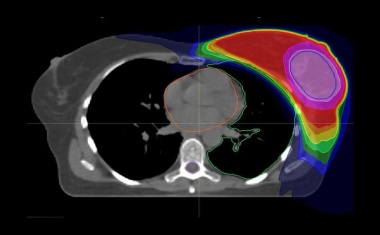

Eine Behandlungsstudie unter Heidelberger Federführung zeigt, dass eine intensivere, dafür kürzere Bestrahlungstherapie nach Brustkrebs-OP ebenso wirksam ist wie die Standardtherapie.